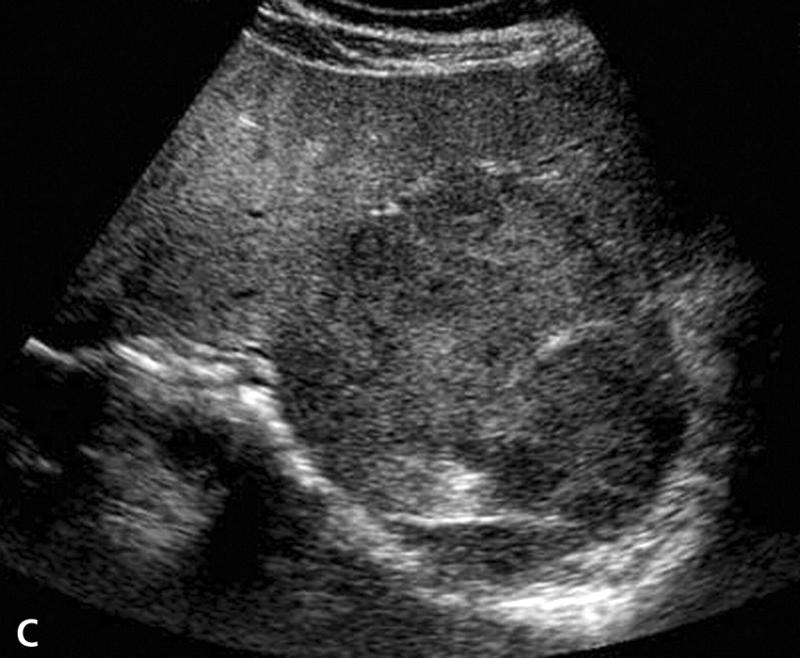

What is the sonographic appearance of Cirrhosis?

Hepatomegaly

Increased echogenicity and attenuation

Size

decrease of right lobe

Size increase of left and caudate

lobe

Nodularity

Fibrosis

Hepatospenomegaly

Ascites

Portal

hypertension

Hepatoma tumors

caudate lobe may be spared